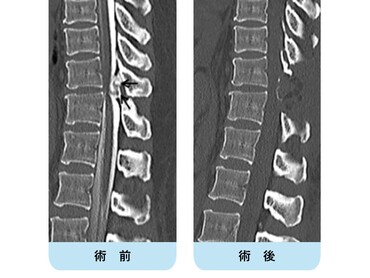

【術前】

CT検査で関節突起部に腰椎分離症を認めています。若年者の腰痛の原因となります。

【術後】

CT検査で関節突起部の骨移植を伴う分離部修復術を施行し骨癒合が得られています。